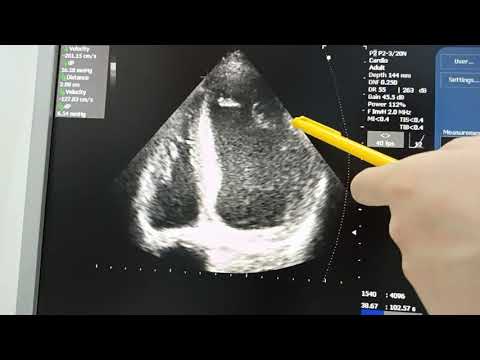

Фракция выброса левого желудочка по Тейхольцу, Симпсону и Думеснилу доплеровский метод

ЭхоКГ FOCUS